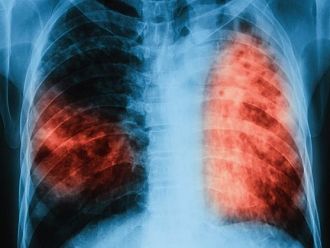

От 9 до 13 декември ще се проведат безплатни прегледи за туберкулоза в лечебни заведения за диагностика и лечение на туберкулоза в областните градове на цялата страна, съобщиха от Министерството на здравеопазването.

По време на „Седмицата на отворените врати“ на всеки желаещ се предлага скрининг за риска от туберкулоза чрез анкета и консултации. На лицата, които са в риск, се провеждат допълнителни прегледи и изследвания. При откриването на случаи на туберкулоза своевременно се предприемат мерки за хоспитализация и лечение, в резултат на което се прекъсва веригата за предаване на инфекцията.